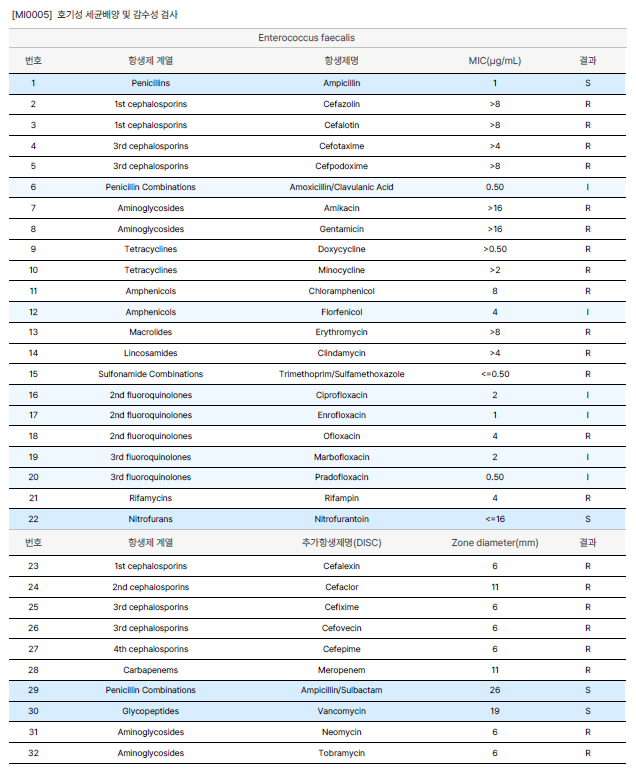

Ascending Hepatic Abscess due to Enterococcus faecalis in a Dog with Persistent Pancreatitis

이 논문에서 주장하는 내용을 가져왔습니다.